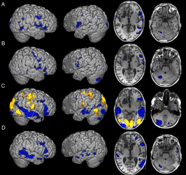

Objective Brain Function Improvements

Perhaps most remarkably, every single patient showed dramatic improvements in objective brain function measures:

Brain Region Activation

• 51.6% improvement in regional brain activation patterns

• Significantly reduced deviation from healthy control standards

• Changes visible on task-related fMRI scans

Functional Connectivity

• 56.9% improvement in inter-region brain connectivity

• Restoration of healthy communication between brain networks

• Normalization of Default Mode Network activity

• Enhanced Cognitive Control Network function

These objective changes provide biological confirmation that the treatment is directly addressing the underlying neural dysfunction—not just masking symptoms.